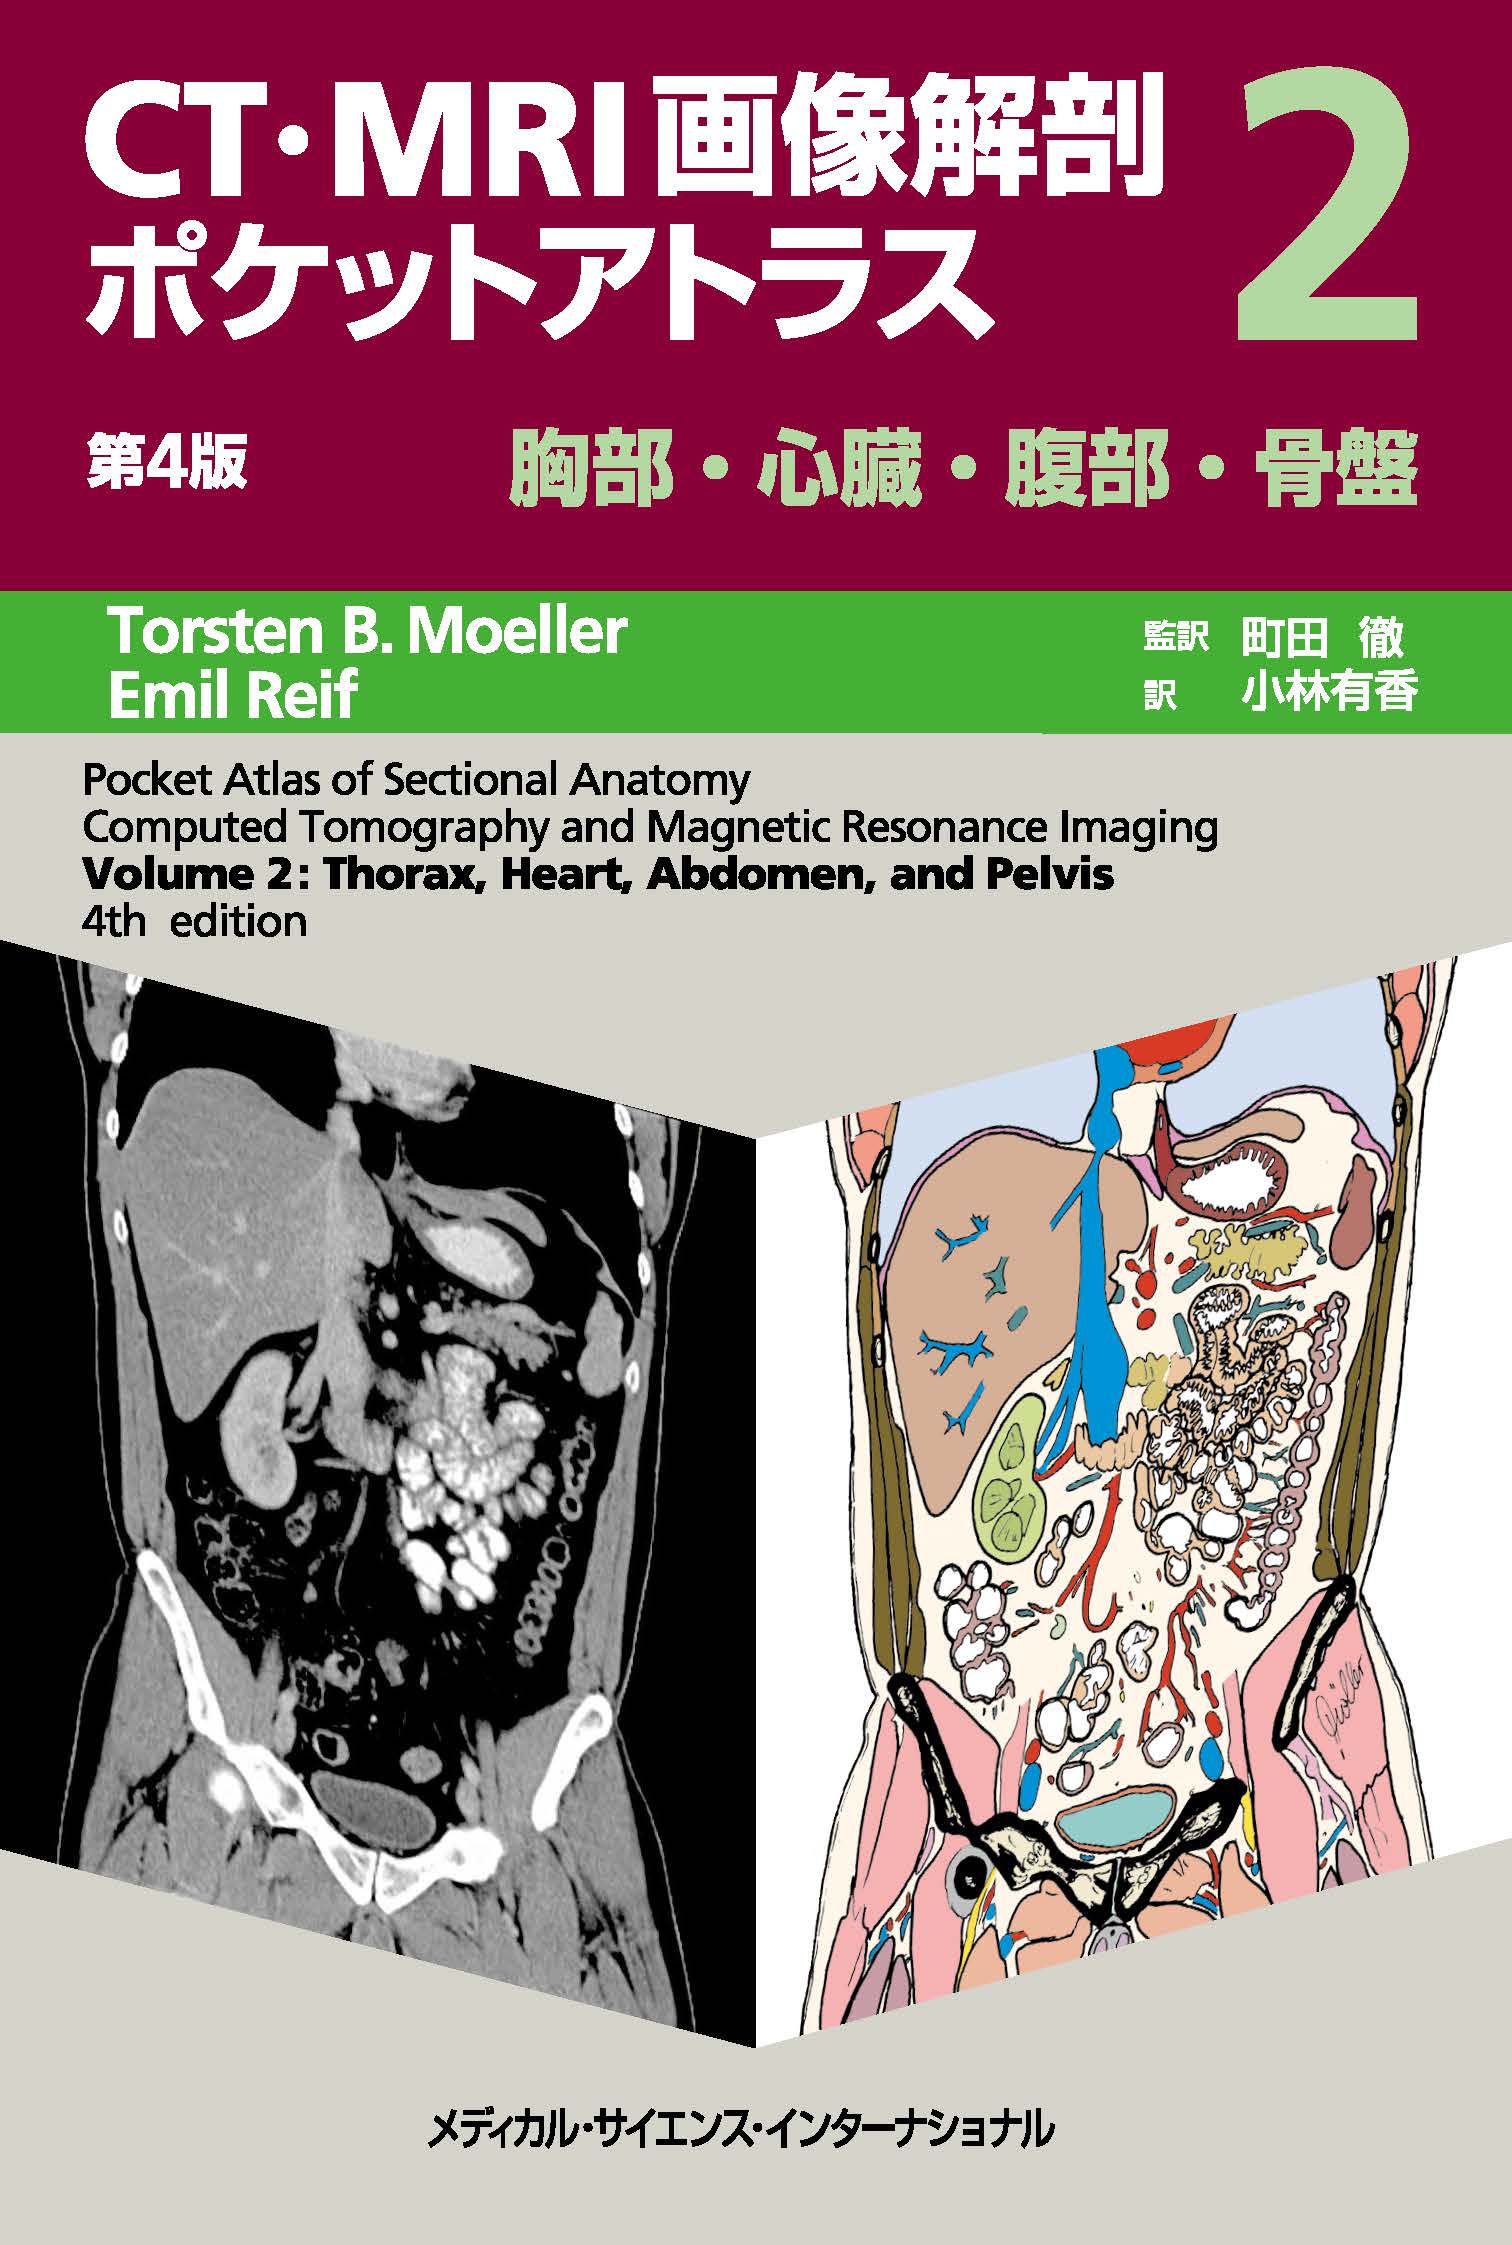

NEW!頭部から胸部の解剖 | 京都科学, CT・MRI画像解剖ポケットアトラス 第4版 2巻 胸部・心臓・腹部,

CT・MRI画像解剖ポケットアトラス 第4版 2巻 胸部・心臓・腹部, 黒澤一弘(かずひろ)解剖学IT教育・指圧師・ラダック on X,